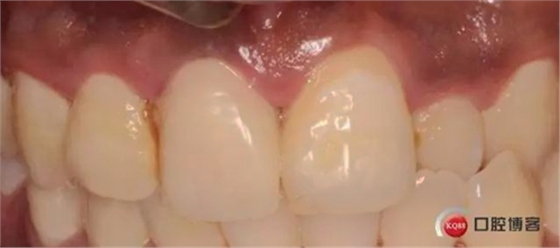

兩個(gè)月后

兩月后牙齦恢復(fù)正常穩(wěn)定。正式取模,E.max鑄瓷修復(fù)

可以看出牙齦袖口很漂亮,修復(fù)體外形也不錯(cuò),就是顏色偏白一點(diǎn),讓患者改色,患者覺得已經(jīng)很滿意了,而且考慮其他牙以后做美白,所以不換了。

可以看出修復(fù)體的邊緣密合度都很好。希望這次修復(fù)能夠讓這顆牙多服役幾年吧